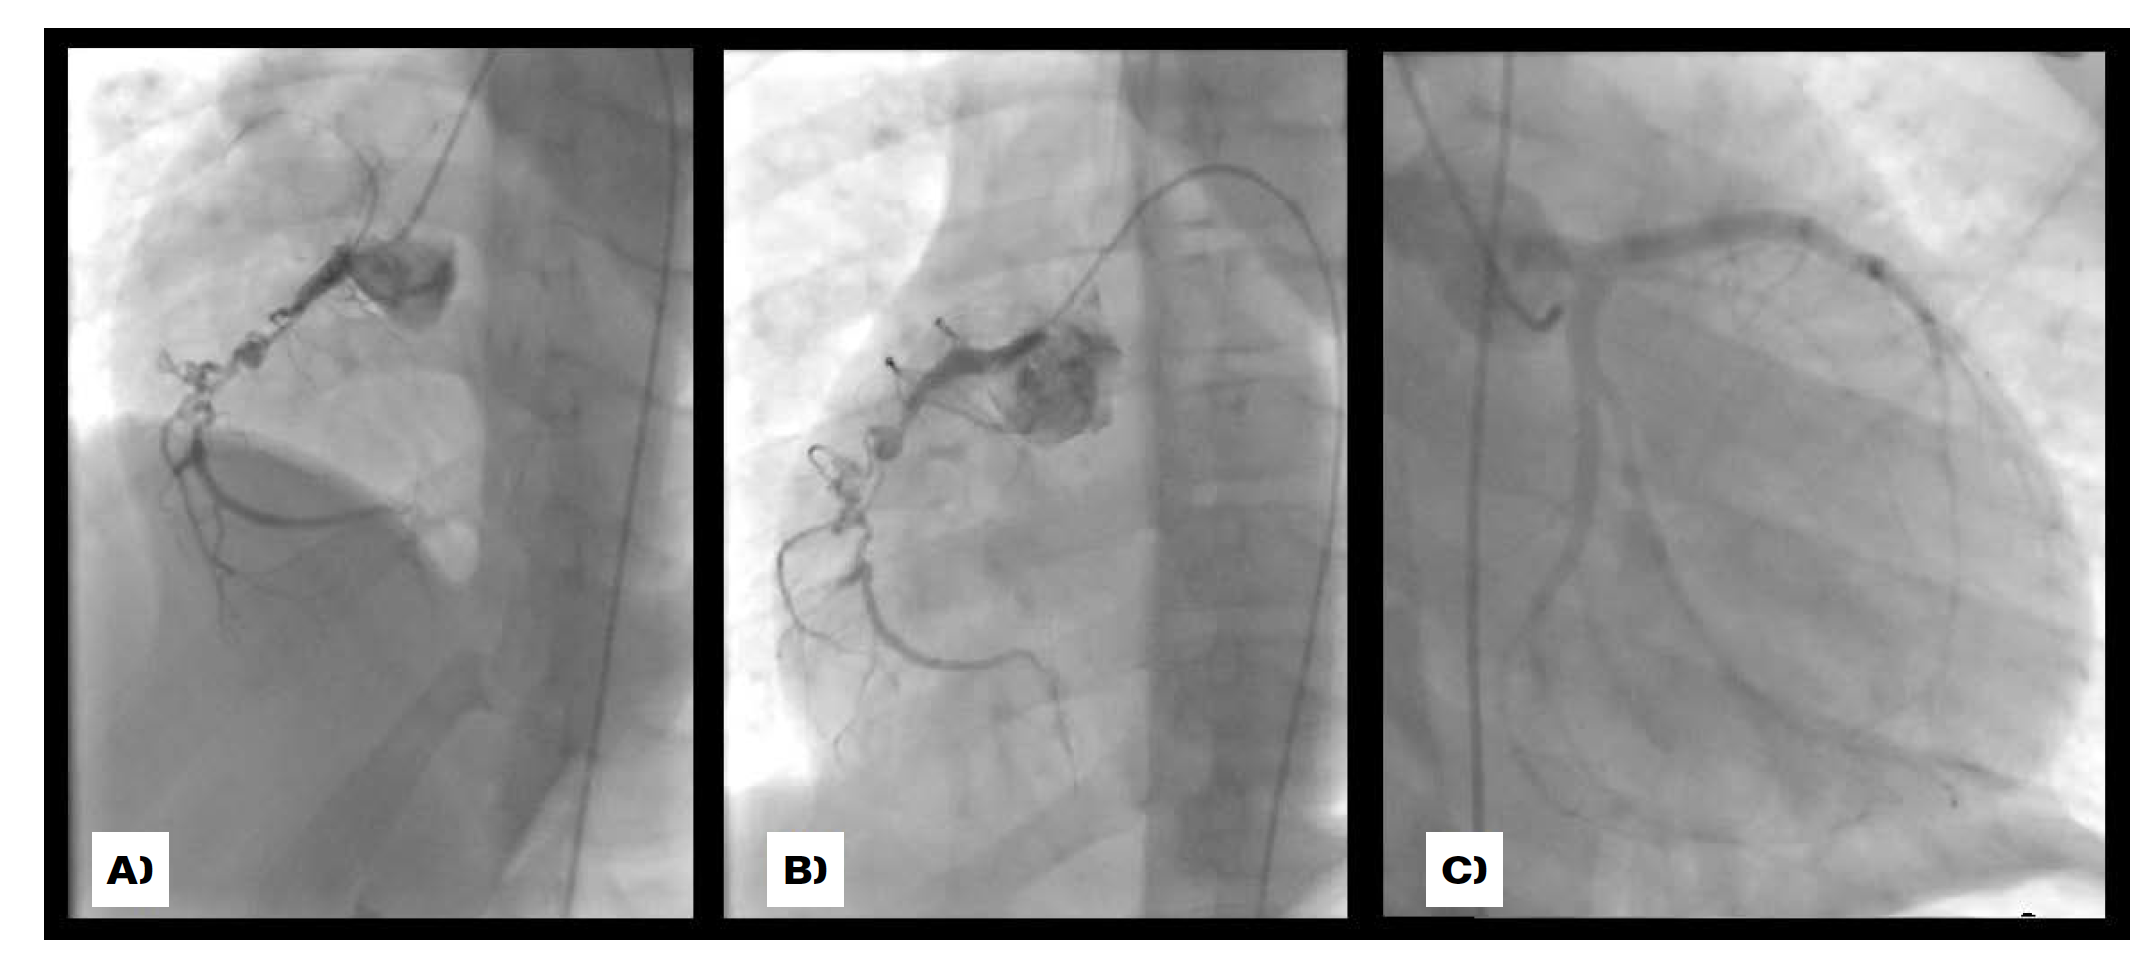

Case 4

A 71-year-old man with history of long-term hypercholesterolemia and systemic hypertension was admitted with a myocardial infarction. The coronary artery angiogram (Figure 5) revealed diffuse dilatation of both coronary arteries and branches with impaired filling and complete occlusion of the middle segment of the left anterior descending artery.

Although from his past medical history we were unable to confirm previous Kawasaki disease, the findings were suggestive.

Regarding our adult patient’s case, coronary artery ectasia is found in about 3-8% of angiographic studies, very rarely affecting all three vessels. With the advent of intravascular ultrasound about 50% of cases are attributed to atherosclerosis, while 10 to 20% are related to inflammatory diseases or connective tissue disorders, such as Kawasaki disease, Ehlers-Danlos syndrome, or ANCA-related vasculitis. A small percentage of cases are believed to be congenital in aetiology.8 Based on his age, it is likely that our patient had atherosclerotic related changes. However, due to its extent, we cannot exclude a previous inflammatory insult as the cause of the coronary artery ectasia.